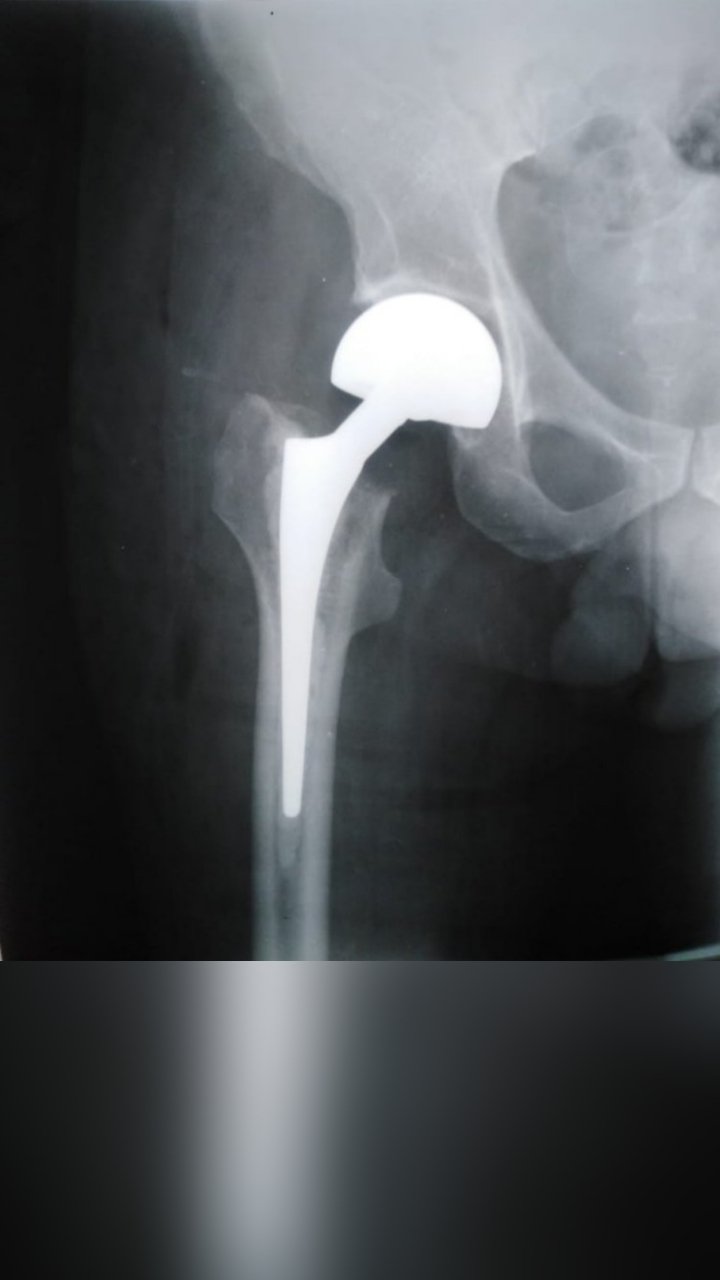

TOTAL HIP REPLACEMENT

BIPOLAR HIP HEMIARTHROPLASTY